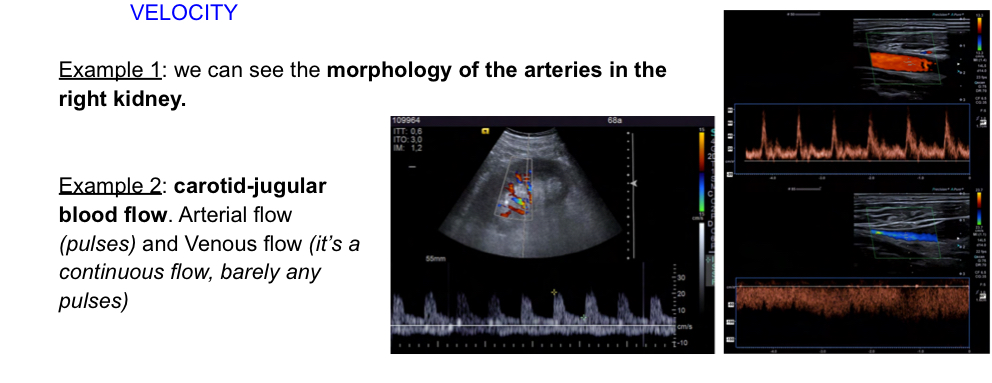

Doppler effecr usage in imaging explain

Can be used to determine blood movement and when color is added to blood moving towards or away from transducer, the imaging can be helpful:

What is a pulsed doppler

Allows to quntify velocity and determine flow direction.. towards tranducer (posittive velocity) away (negative).